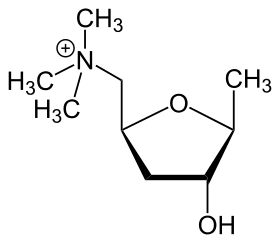

Muscarine[146]

|

Glutamic acid → 3-ketoglutamic acid → muscarine (with pyruvic acid)[147] | Muscarine, allomuscarine, epimuscarine, epiallomuscarine[146] | |